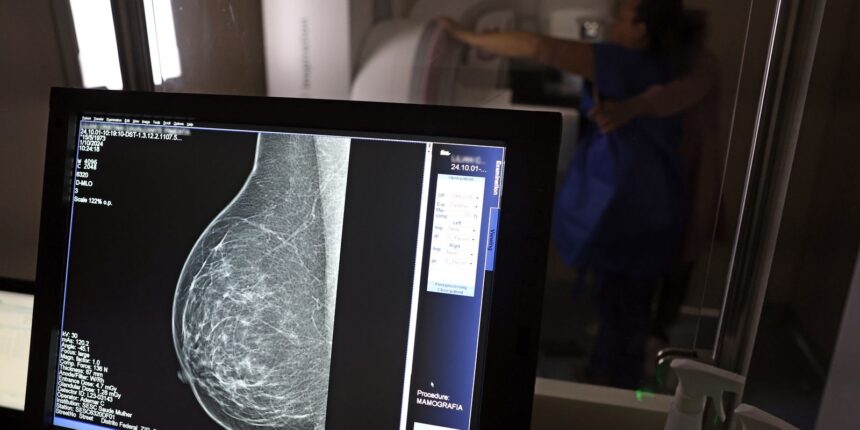

Diante destas descobertas, a Federação Brasileira de Instituições Filantrópicas de Apoio à Saúde da Mama (Femama) reforça a recomendação para que o exame preventivo, a mamografia, seja realizado a partir dos 40 anos. A mamografia, um exame radiográfico, é capaz de detectar nódulos e lesões em estágio inicial, muitas vezes antes que se tornem palpáveis.

A detecção precoce é a chave para aumentar as chances de sucesso no tratamento do câncer de mama. A mamografia, como principal ferramenta de rastreamento, possibilita identificar alterações suspeitas em estágio inicial, permitindo intervenções terapêuticas mais eficazes e, consequentemente, elevando as taxas de cura e melhorando a qualidade de vida das pacientes. A conscientização sobre a importância do rastreamento e o acesso facilitado à mamografia são passos essenciais para combater esta doença.